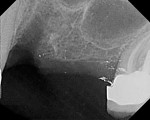

A 65-year-old woman had recently lost a fractured tooth No. 12, which was the anterior abutment for a fixed prosthesis extending to No. 15 (Figure 16). The CBCT cross-sectionals revealed a vertical and horizontal bone deficiency at No. 12, a narrowed ridge at site No. 13, and 2 mm of subantral bone at site No. 14 (Figure 17). The patient was informed she would need vertical and horizontal augmentation as well as sinus elevation prior to implant placement at site Nos. 12, 13, and 14.

Antibiotic therapy (amoxicillin 1.5 g/day) was initiated 1 day prior to surgery. A crestal incision in combination with a vertical release on the mesial aspect of No. 11 permitted broad mucoperiosteal flap reflection. Small cortical perforations were created in the buccal plate at site Nos. 12 and 13 to increase vascularity at the augmented site. Osteotomies measuring 2 mm in diameter and 3 mm in depth stabilized two 7-mm long pins positioned to support vertical and horizontal bone growth. A small oval lateral window was created at site No. 14 for sinus augmentation (Figure 18). The ridge at site Nos. 12 and 13 was grafted with a 4:1 combination of Regenaform and bovine bone mineral (NuOss®, Ace Surgical Supply Co., www.acesurgical.com) and the sinus grafted with L-PRF and NuOss. The grafted sites were first covered with four L-PRF membranes (Figure 19), then two pericardium membranes (CopiOs® Pericardium Membrane, Zimmer Dental, www.zimmerdental.com), followed by the final layer of L-PRF.